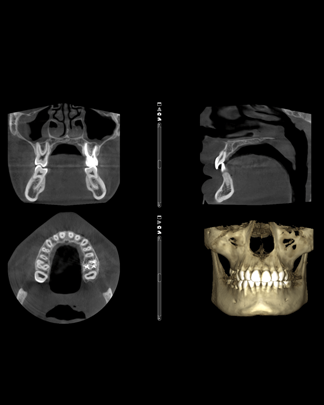

Contamos con un equipo de CBCT (radiografías en 3D ) Esta tecnología nos ayuda a examinar más detalladamente las estructura que componen tu boca , empleando mucha menor radiación y muchas más presión y nitidez, para logra mejores diagnósticos y poder hacer una planificación más exhaustiva de tus tratamientos.